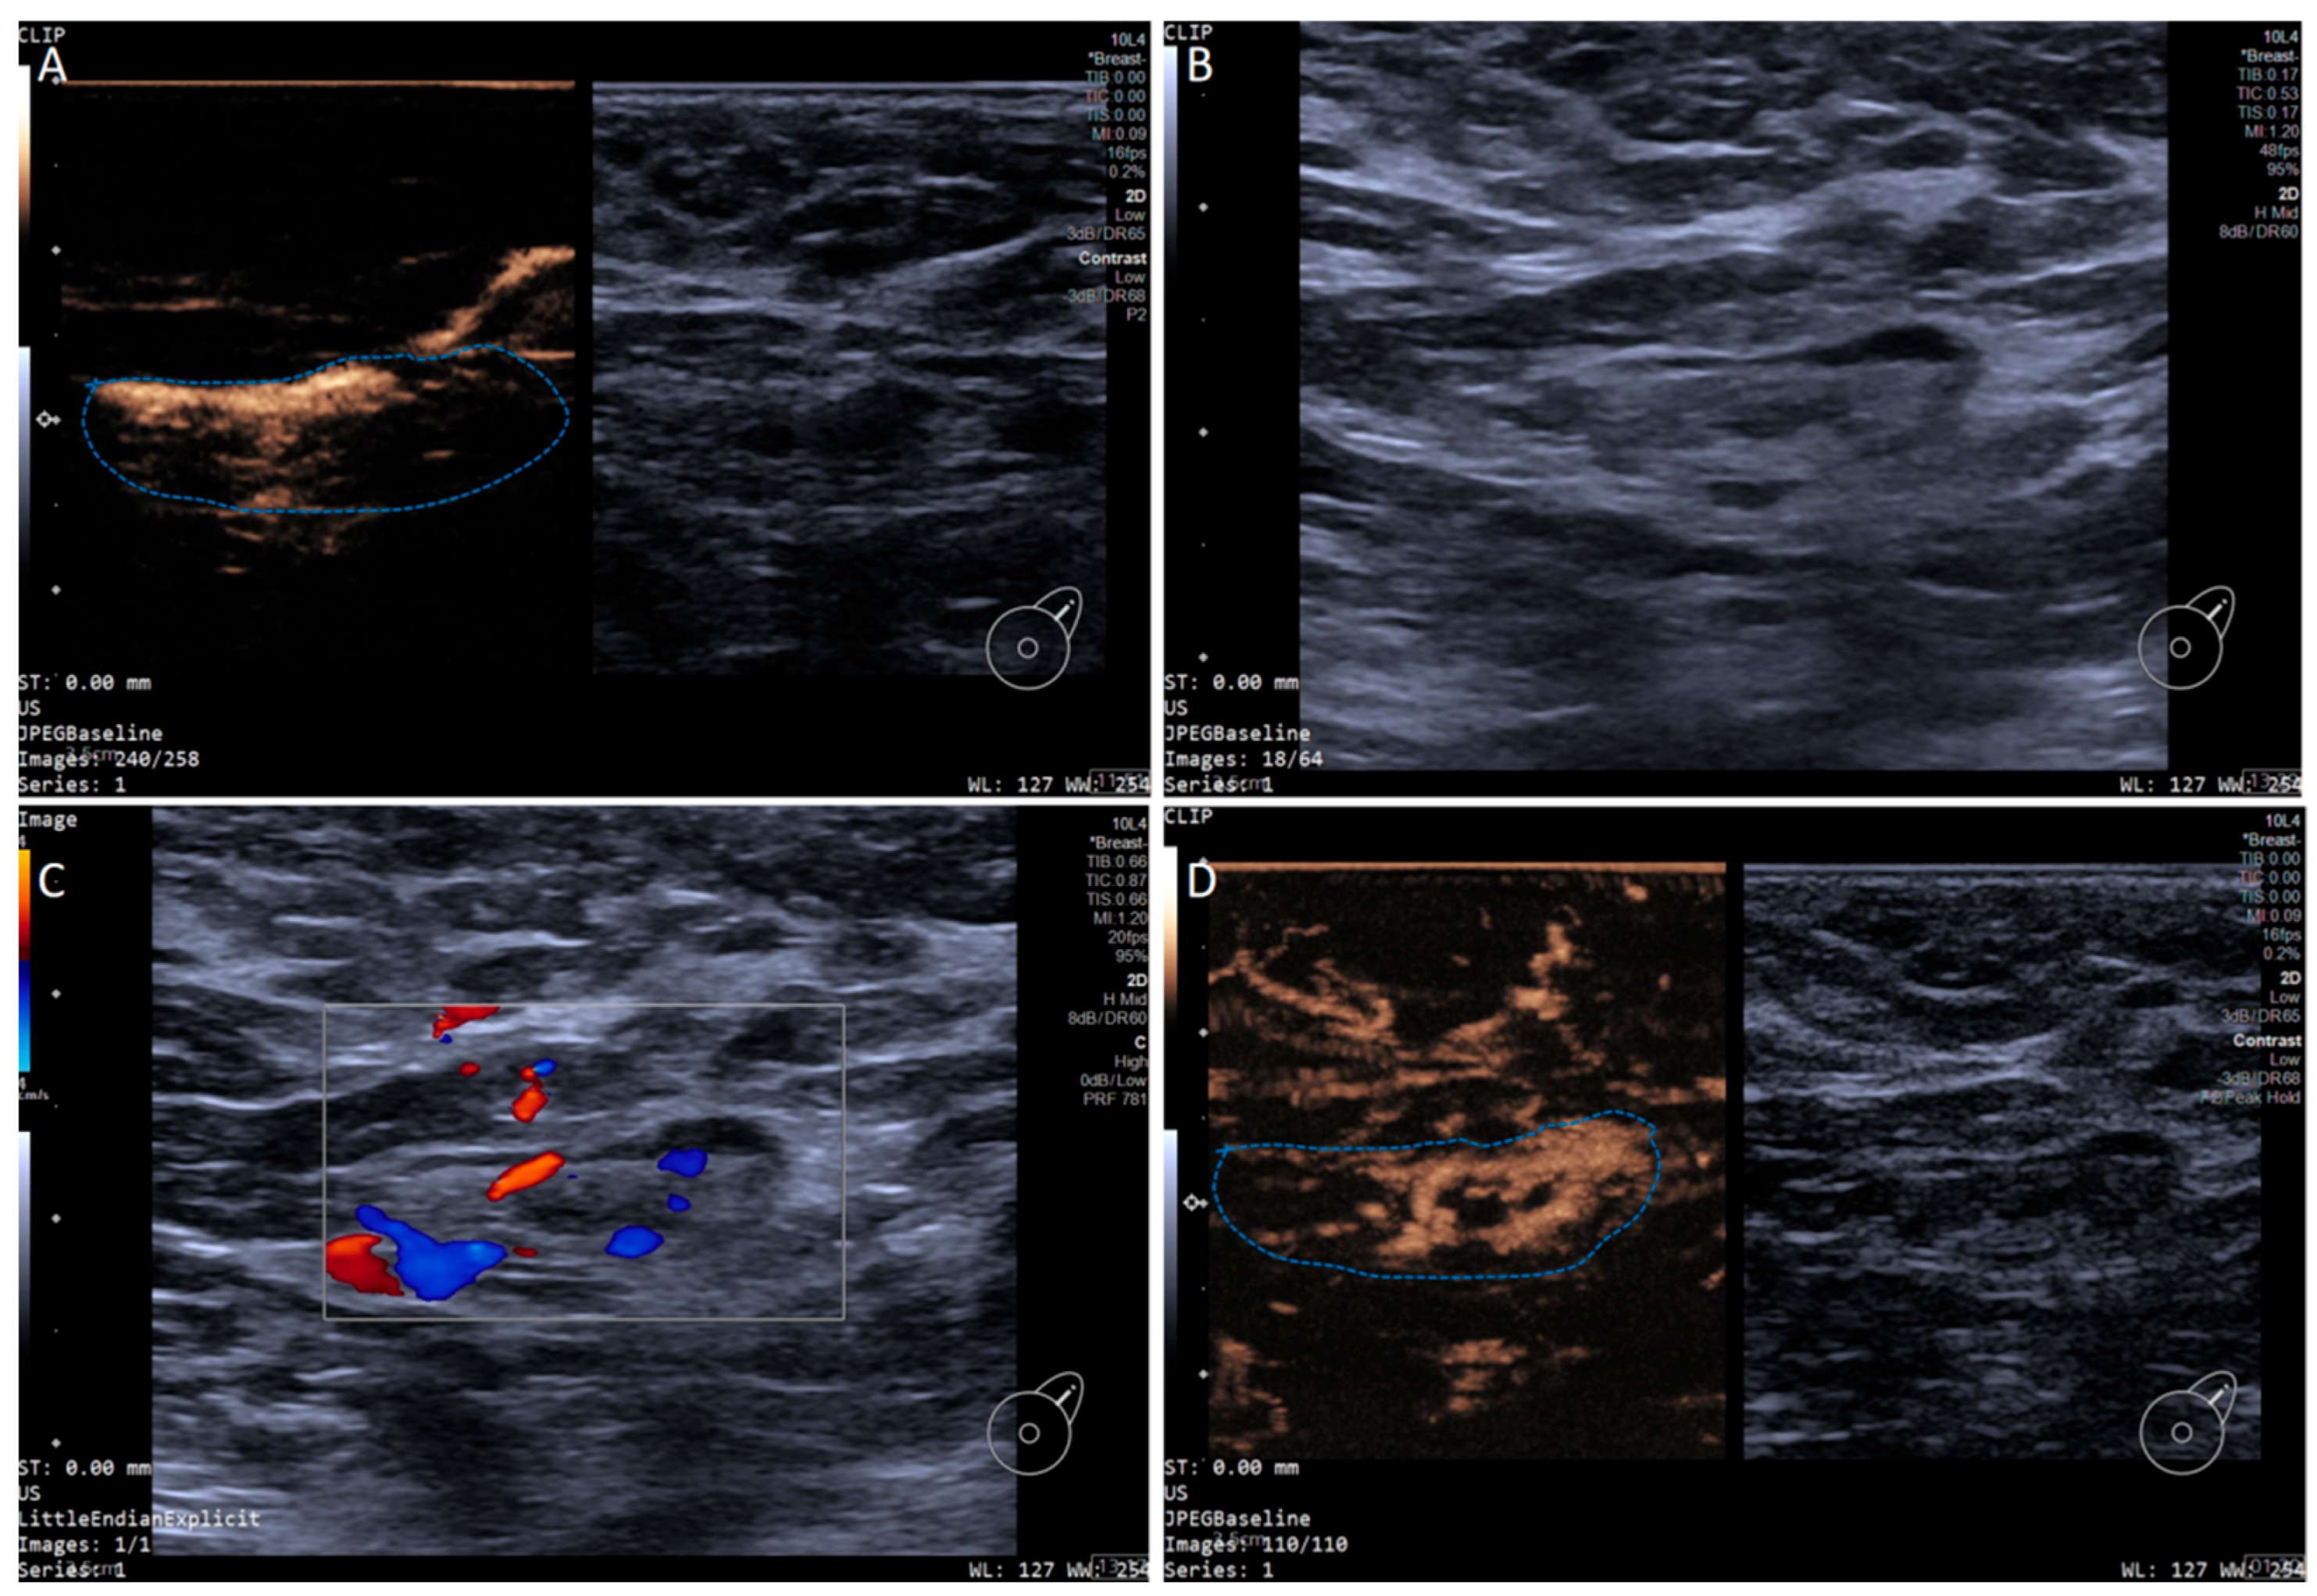

In addition, the SLN-IVCEUS enhancement patterns were divided into four types: type I showed homogeneous high enhancement; type II showed diffuse inhomogeneous high enhancement; type III showed no/low enhancement of the lymphatic hilus, homogeneous high enhancement of the cortex; type IV showed part of the cortical filling defect, low enhancement or high enhancement, the rest showed the performance of types I, II or III. And SLN-IVCEUS enhancement sequence was divided into three types based on the orders of bubbles entering the lymph nodes: centrifugal enhancement, centripetal enhancement, and diffuse enhancement. A malignant lymph node was diagnosed as long as one of the following conditions was met: (I) centripetal enhancement; (II) diffuse enhancement; (III) the enhancement mode of IVCEUS was type IV. SLN was diagnosed as malignant when PCEUS and/or IVCEUS diagnosed the SLN as malignant (Figure 2 and Figure 3).

Figure 2. Multimodal ultrasound imaging of pathologically confirmed non-metastatic sentinel lymph node. (A) Intradermal CEUS image (the enhancement pattern is type VIc, the blue dotted line delineates the contour of the SLN); (B) 2D US image; (C) Color Doppler Flow Imaging (CDFI) image; (D) intravenous CEUS image (the enhancement pattern is III, the blue dotted line delineates the contour of the SLN).